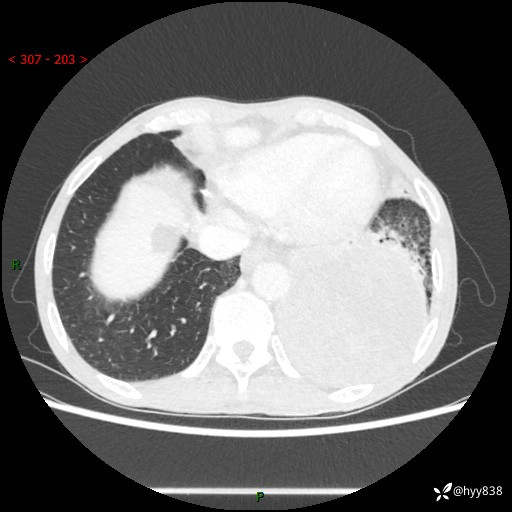

77岁/男,腹痛2月,CT发现左肺占位1天。巨大肿块,肺内或肺外来源…结果公布~

主诉:腹痛2月,CT发现左肺占位1天

现病史:患者于2025年9月间断左下腹胀痛,在当地镇卫生院行彩超检查考虑泌尿系结石,行止痛排石对症治疗未见明显好转;1天前腹痛症状加重,至当地市第三人民医院行CT检查:左肺下叶巨大团块状软组织影,考虑肿瘤性病变,建议增强CT检查;左侧胸腔积液;纵膈内淋巴结肿大;双肺肺气肿;右肺中叶纤维灶。为进一步求治,来我院就诊。

胸部CT平扫+增强